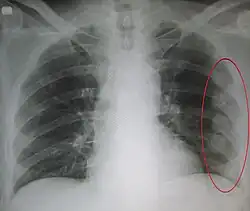

Verletzungen der Lunge können neben einer Lungenkontusion als Quetschverletzung Lungenrisse sein. Letztere führen zu einem Pneumothorax, wie er bei 10 bis 50 Prozent der Patienten mit Thoraxtrauma auftritt,[6] und gegebenenfalls zu einem Spannungspneumothorax. Blutungen in den Thorax hinein führen zu einem Hämatothorax. Bei einem Hämatopneumothorax treten sowohl ein Pneumo- als auch ein Hämatothorax in Kombination auf. Symptome sind zunächst Luftnot und je nach Ausmaß der Blutung auch Kreislaufinstabilität. Bei einem Pneumothorax kann sich insbesondere bei Ausbildung eines Spannungspneumothorax ein Hautemphysem bilden, das eine große Ausdehnung erreichen kann. Therapie ist eine Entlastung der Pleurahöhle mittels Thoraxdrainage auf der betroffenen Seite. Üblicherweise kommen kleinere intrathorakale Blutungen von alleine zum Stehen, so dass außer einer Drainage keine weiteren Maßnahmen notwendig werden. Eine Thorakotomie zur operativen Blutstillung kann bei einem initialen Blutverlust von mehr als 1.500 ml nach der Thoraxdrainage oder bei einem fortwährenden Blutverlust von mehr als 250 ml pro Stunde über mehr als vier Stunden erfolgen.[2][5]